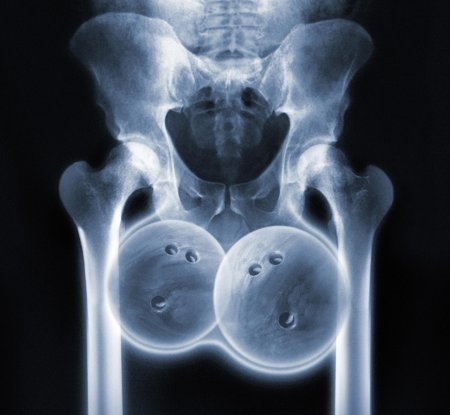

Рентгеновский эффект создает фантастические композиции в этих фотографиях девушки, чье тело становится прозрачным, демонстрируя скелет и внутренние органы. Она позирует в разных позах, ее силуэт светится загадочным свечением. Каждый кадр передает атмосферу научной фантастики и медицинского искусства. Ее кожа кажется полупрозрачной, позволяя увидеть кости и мышцы. Фотографии рассказывают о хрупкости человеческого тела и его внутренней красоте. Девушка то стоит в задумчивости, то делает грациозное движение. Эти иллюстрации вдохновляют на размышления о человеческой анатомии и уязвимости. Каждая картинка - это момент прозрения, когда внешнее уступает место внутреннему. Девушка воплощает образ современной Медузы, сочетающей красоту и загадочность.

Сквозь материю: тайны анатомии